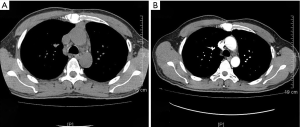

On January 15th in 2019, a 42-year-old male was referred to our hospital, complaining of chest pain and tightness for over 1 month, and the symptoms were getting worse gradually in the last week. He had no history of malignancy, and tumor family history, as well as genetic history, was not found. The patient reported no fever, cough, hemoptysis, difficulty swallowing, dyspnea, hoarseness and limb weakness. No positive signs were detected in routine physical examination and tumor markers were normal, such as carcino-embryonic antigen (CEA), ferritin (FER). Chest CT revealed a large left-anterior mediastinum mass. Further evaluation demonstrated a 115 mm × 95 mm mass with patchy necrosis, heterogeneous enhancement and small blood vessels. Moreover, the large mass compressed left brachiocephalic veins, pericardium and upper-lobe of left lung (Figure 1). Based on clinical and CT appearances, the patient was suspected of invasive thymoma or thymic carcinoma pre-operatively. Due to the estimated great-difficulty by video-assisted thoracoscopic surgery (VATS), median sternotomy was performed to remove the tumor in January 30th, 2019. During the surgery, we found that the tumor was located in the left-anterior mediastinum with incomplete capsule, and that part of upper-lobe of left lung was compressed by the large mass. Complete tumor resection with combined reginal mediastinal lymph node dissection were performed. Hematoxylin-eosin (HE) staining showed that the tumor cells were arranged in a nested, or ribbon pattern, with mild atypia, local hemorrhage, foci of necrosis and abundant interstitial blood vessels (Figure 2). Immunohistochemistry demonstrated positivity for CD56, Syn, CgA, CK (Figure 3A,B,C,D), and staining indices for Ki-67 was 15% (Figure 3E). No metastasis was found in all the 4 resected mediastinal lymph nodes. Postoperative pathology turned out to be primary TAC, Masaoka stage II (7). Postoperative chest CT (Figure 4A) showed that the tumor was resected completely and no recurrence occurred in postoperative follow-up (Figure 4B). From March 3rd on, a total of 6 cycles of postoperative adjuvant chemotherapy was given per 3 weeks successfully, and the chemotherapy regimen was gemcitabine (1,000 mg/m2 on 1st day) plus cisplatin (80 mg/m2 on 1st day). No 3/4 grade adverse effects (AEs) occurred during the perioperative period. There was no tumor recurrence or metastasis during the postoperative follow-up. A time lime showed the whole medical procedure of the special case (Figure 5).